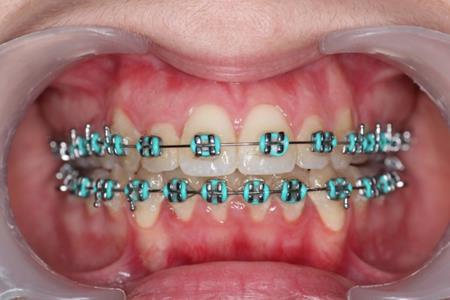

Figure 5.Intraoral photography after the mini-implant activation

In this case the implants were loaded after one week with a 100-150 force using an elastic chain.

The intrusion rate obtained was 0,5-1 mm per month without root resorbtion or vitality problems.

Tongue therapy was performed.